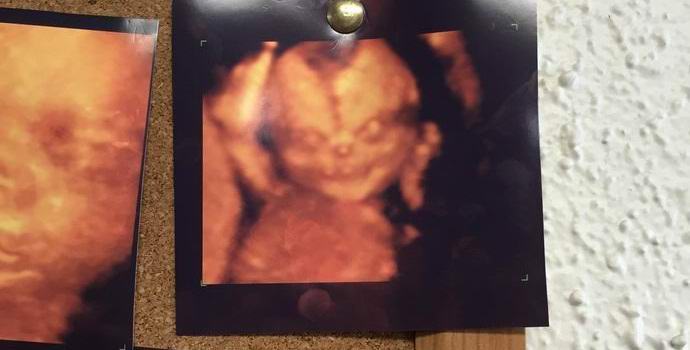

Снимка от отворени източници Потребители на сайта за социални новини „Reddit“ активно обсъжда снимка на получено неродено бебе чрез ултразвук. Според автора на новините, фотографията висеше на стената на медицинското заведение, където се появи с жена му да изследва собствения си потомък.

Авторът пише: „Съпругата ми и аз дойдохме в клиниката, за да направим ултразвук изследване на нашето дете. Когато видяхме това изображение, окачена на стената, жена ми веднага промени решението си за извършване на ултразвуково сканиране. Така е и така тя се уплаши. Имаше много снимки на деца и то всички бяха от същия тип, без никакви плашещи характеристики. Обаче това може да се нарече картина, която се откроява сред другите наистина ужасно. Трудно е да си представим емоциите на родителите който видя такова демонично лице по време на ултразвуковата процедура нероденото му дете.

Фотографията предизвика разгорещени дискусии сред редовите членове на ресурса. „Чудя се дали има такава услуга като вътрематочна екзорцизъм? “- интересува се един потребител.” Толкова малък, но вече абсолютно зло – пише друг. „Погледнете по-отблизо вдясно ръка. Наистина ли има бутилка бира? ” коментатор.

Потребителите на Reddit сравниха героя на снимката с кукла Чъки от известен филм на ужасите и дори с антихриста. Макар, по-скоро общо, това е обикновено дете, което е било заловено по време на ултразвук в пълно лице, което, между другото, доста рядко. Оттук и плашещата необичайност на фотографията. Човек може само да се надява, че родителите на това бебе не са те не притежават предразсъдъци.